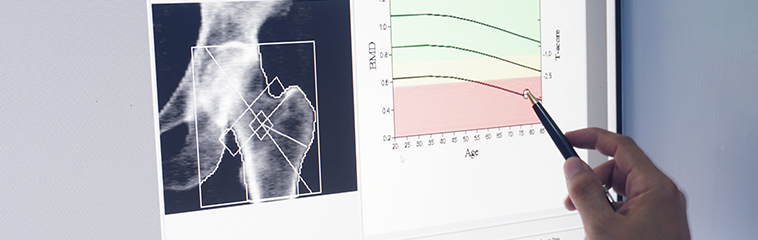

La densidad mineral ósea es el parámetro utilizado para la evaluación de la osteoporosis. De esta manera, la Organización Mundial de la Salud (OMS) emplea el T-score (comparación de la densidad mineral ósea obtenida con la correspondiente a una persona jóven de referencia) para evaluar los diferentes grados de daño en el tejido óseo, estableciéndose la siguiente clasificación:

- T-score comprendido entre +1 y -1 DS: masa ósea normal

- T-score comprendido entre -1 y -2,5 DS: osteopenia

- T-score ≤ -2,5 DS: osteoporosis